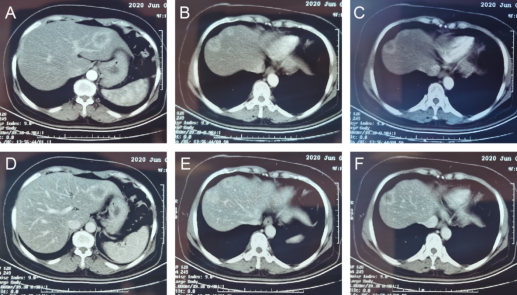

然而,治疗的过程并非一帆风顺,王阿姨在完成第2周期Xelox+贝伐珠单抗治疗后出现腹痛、便血及肠梗阻症状,由于病情变化结直肠肿瘤MDT团队再次进行讨论。此次讨论中认为患者原发灶症状明显,应中止内科治疗,考虑外科介入。复查肝胆脾256排增强CT,未见新增转移病灶,三处肝转移灶为初始可切除,可试行同期手术。因此,结直肠肿瘤MDT团队拟定为阿姨实施结肠癌和肝转移瘤同期手术治疗,期望通过一次手术达到根治,术后再根据病理情况继续全身治疗。

图1 复查肝胆脾256排增强CT结果